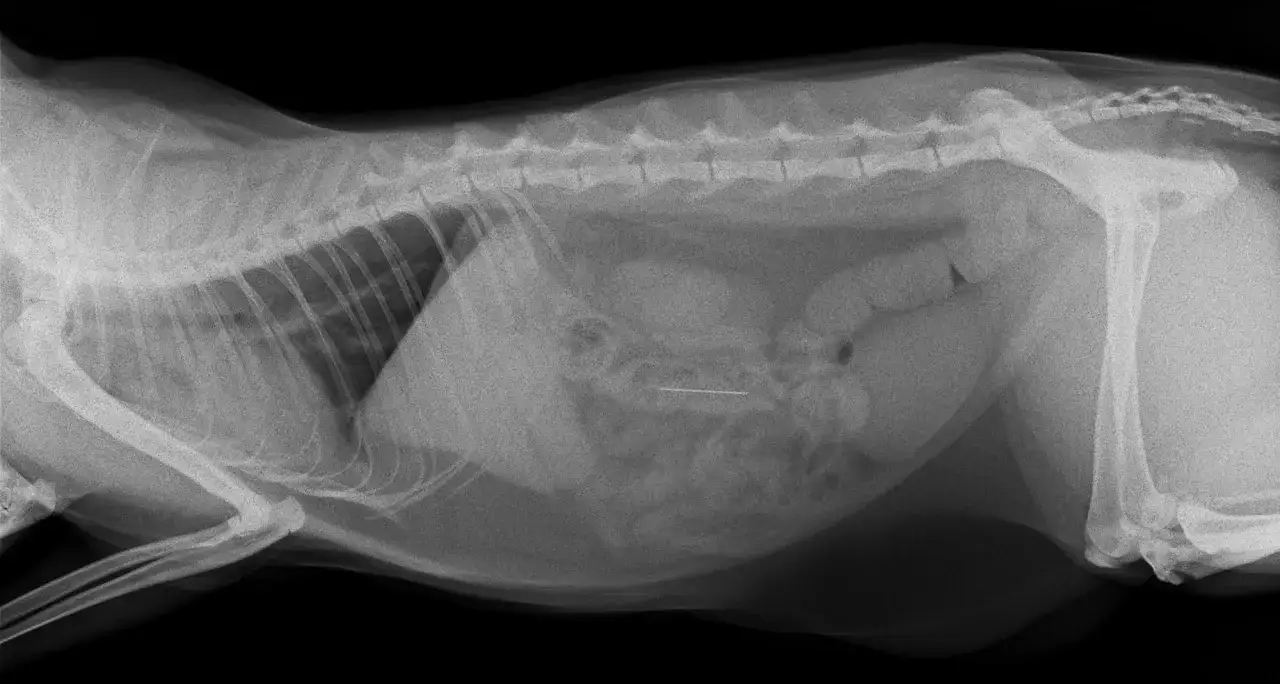

Niewidoczne zniszczenia: Jak udar cieplny wpływa na inne narządy wewnętrzne?

Często skupiamy się na mózgu, gdy mówimy o udarze cieplnym, co jest zrozumiałe. Jednak jako weterynarz muszę podkreślić, że udar to problem ogólnoustrojowy, który może prowadzić do rozległych uszkodzeń wielu narządów wewnętrznych. Te "niewidoczne zniszczenia" mogą być równie niebezpieczne, a ich objawy mogą pojawić się nawet po kilku dniach od udaru, kiedy właściciel myśli, że najgorsze już za psem.

Ostra niewydolność nerek ciche zagrożenie po przegrzaniu

Nerki są niezwykle wrażliwe na niedotlenienie i wysokie temperatury. Udar cieplny może prowadzić do ostrej niewydolności nerek, co jest stanem zagrożenia życia. Uszkodzenie nerek może objawiać się zmniejszoną produkcją moczu lub jej całkowitym brakiem, a także gromadzeniem się toksyn w organizmie. Co ważne, objawy niewydolności nerkowej mogą pojawić się nawet 3 do 5 dni po wystąpieniu udaru. To dlatego tak ważne jest, aby pies był pod stałą opieką weterynaryjną i monitorowany przez dłuższy czas, nawet po pozornym powrocie do zdrowia.

Uszkodzenia układu krążenia i pokarmowego na co zwrócić uwagę w trakcie rekonwalescencji?

Układ krążenia również cierpi podczas udaru. Może dojść do zaburzeń rytmu serca, a nawet do DIC (rozsianego krzepnięcia wewnątrznaczyniowego), co jest bardzo poważnym powikłaniem, prowadzącym do krwawień i zakrzepów w całym organizmie. Układ pokarmowy także jest narażony często obserwujemy krwotoczne zapalenie jelit, objawiające się krwawą biegunką i wymiotami.

Rola badań krwi w ocenie skali uszkodzeń po udarze

Badania krwi są absolutnie kluczowe w ocenie skali uszkodzeń wewnętrznych po udarze cieplnym. Pozwalają nam, weterynarzom, "zajrzeć" do wnętrza organizmu i ocenić funkcjonowanie poszczególnych narządów. Monitorowane są takie parametry jak:

- Kreatynina i mocznik wskaźniki funkcji nerek.

- Enzymy wątrobowe (ALT, AST) wskazujące na uszkodzenie wątroby.

- Parametry krzepnięcia krwi w celu wykrycia DIC.

- Elektrolity ich zaburzenia są częste po udarze.

- Morfologia krwi ocena stanu zapalnego i odwodnienia.

Regularne badania krwi w trakcie rekonwalescencji pozwalają na wczesne wykrycie powikłań i wdrożenie odpowiedniego leczenia, co znacząco poprawia rokowania.